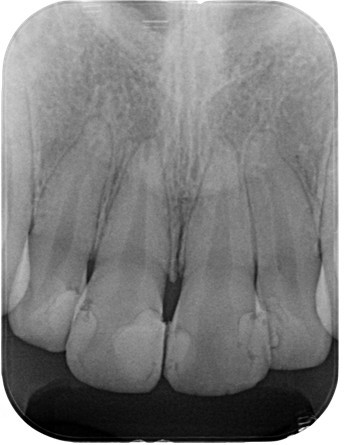

(図28)初診時レントゲン像

右上1番の歯冠部は広範囲にわたってCRが充填されている

根尖部の形態はラッパ状を呈していて未完成であることが確認できる

左:初診時 右:術直後